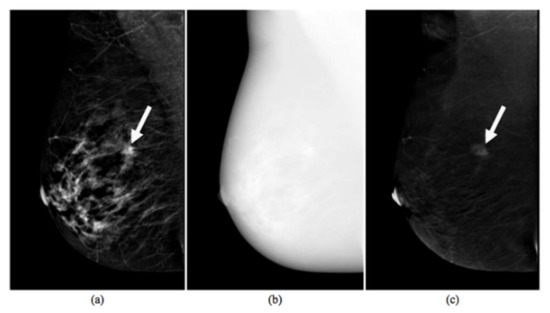

2.2. CESM Examination